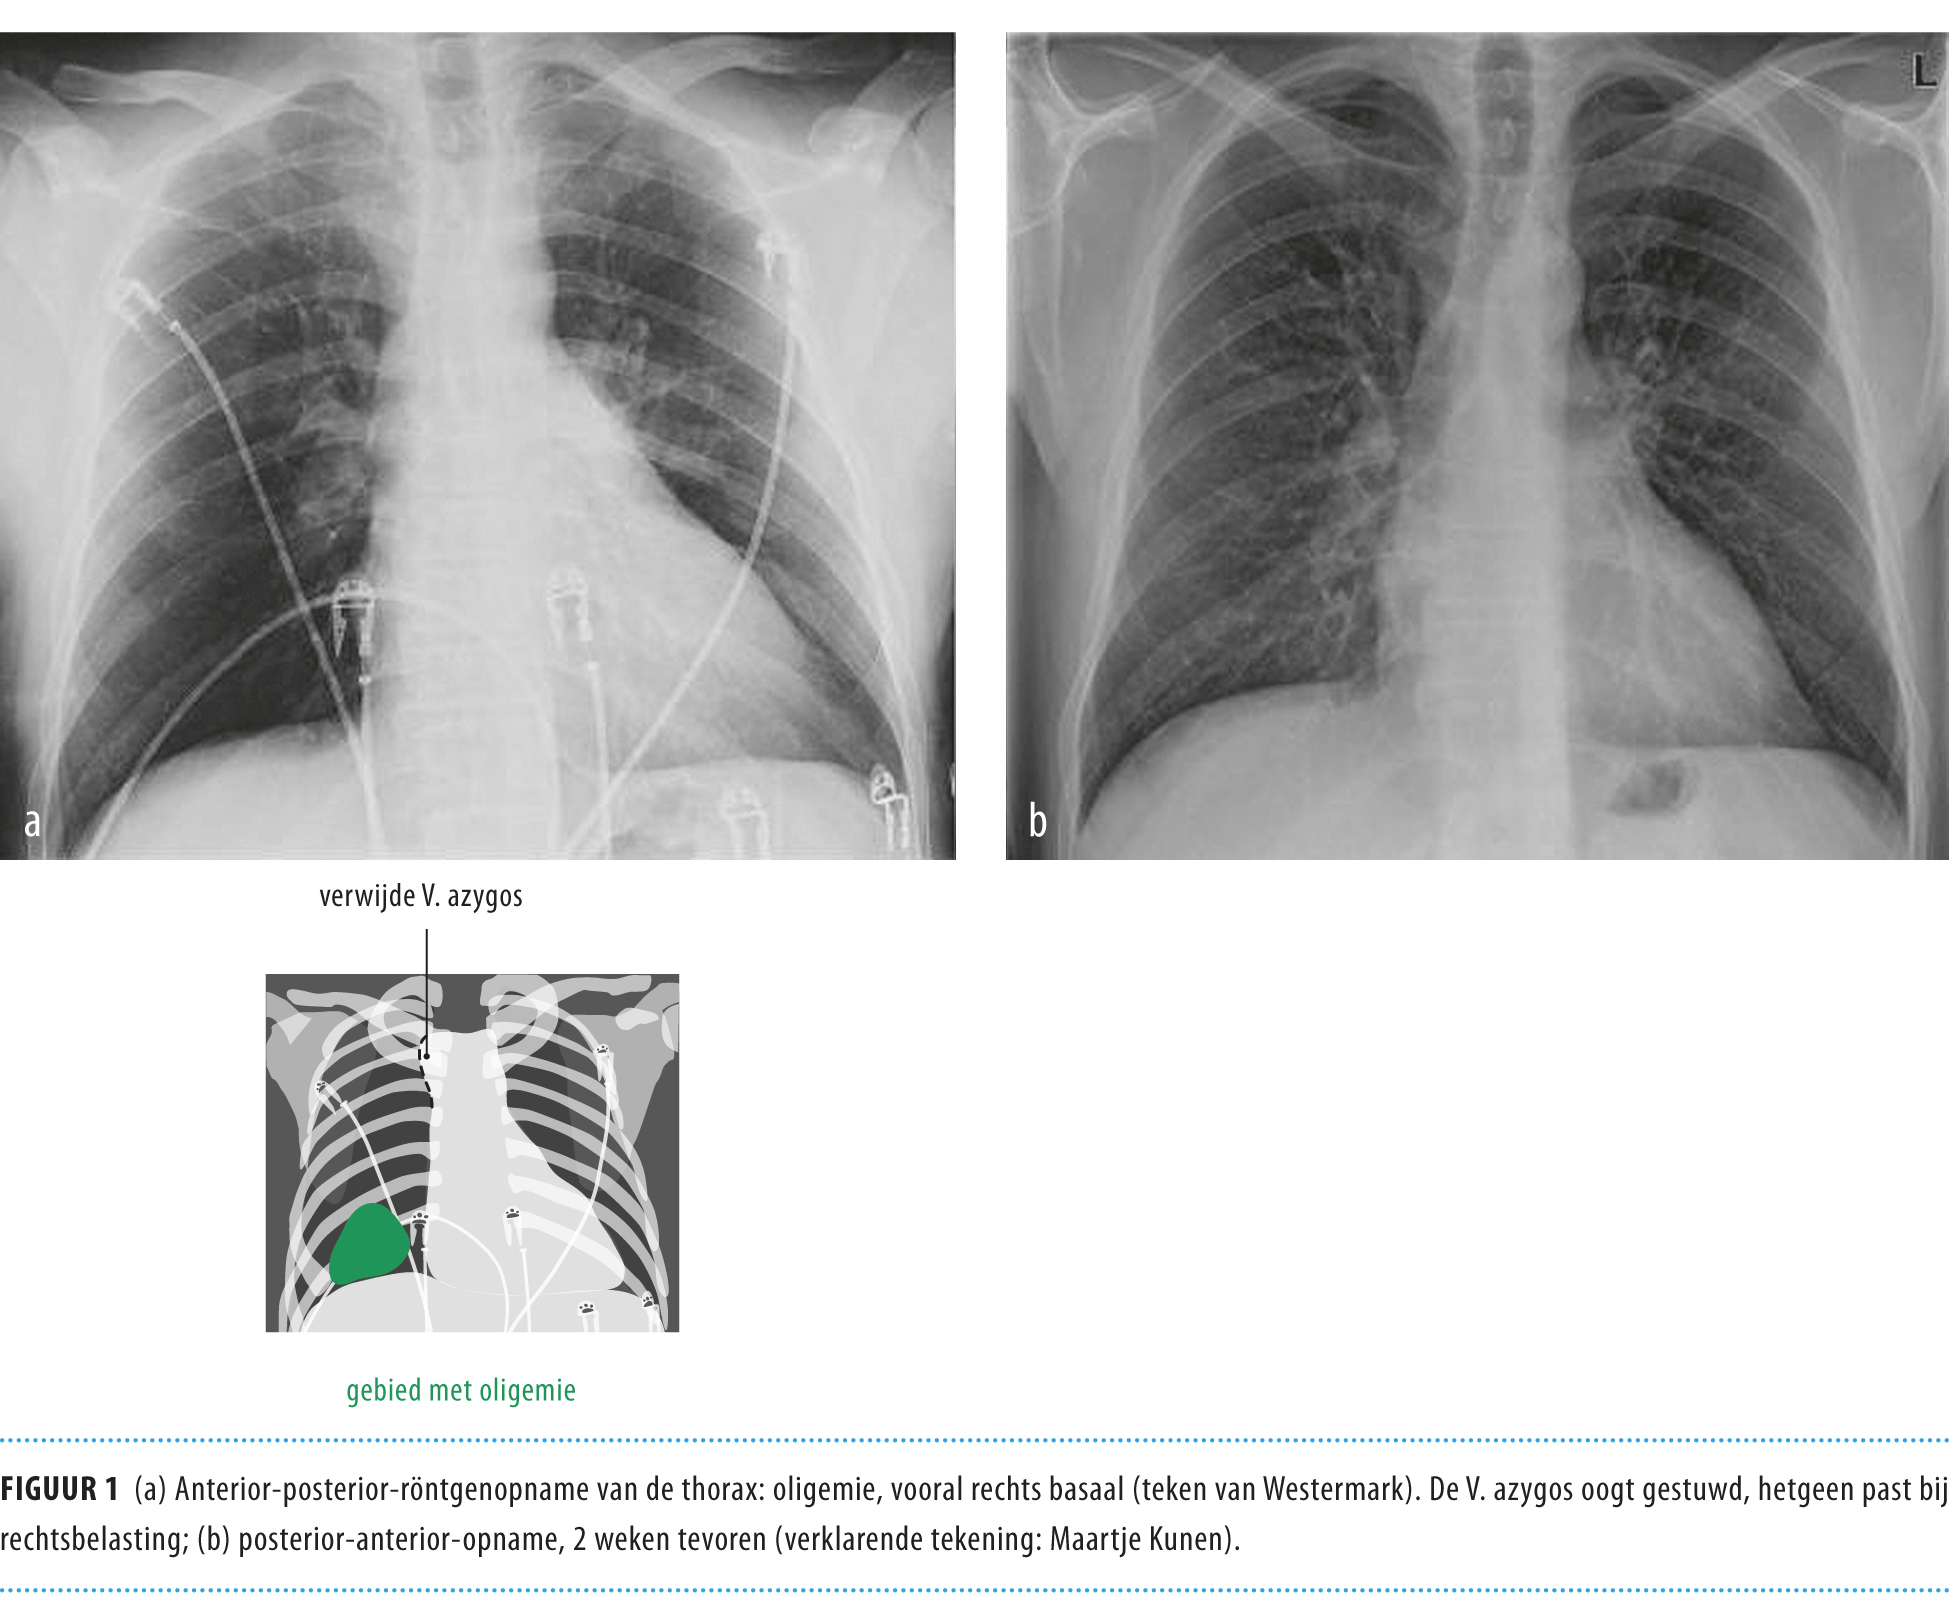

Een 80-jarige vrouw met kortademigheid door myxoma cordis ...

Een 80-jarige vrouw met kortademigheid door myxoma cordis ... from www.ntvg.nl